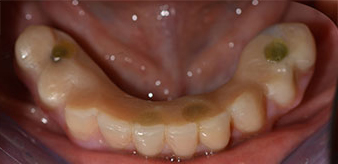

Die 64-jährige Patientin wurde mit einer Unterkiefer-Restbezahnung 38, 33 und 43 und einer klammerbefestigten Interimsprothese im Unterkiefer vorstellig (Abb. 1 und 2).

Unterkiefer-Restbezahnung

Abb. 2